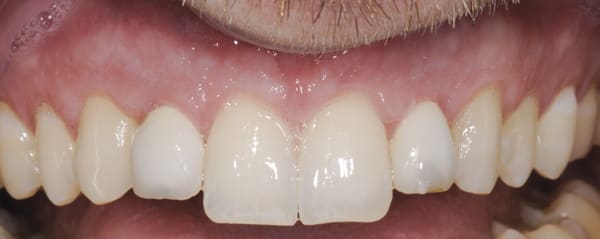

Both provisional restorations were removed, the definitive abutments were connected, and the abutment screws were torqued to 35 Ncm. The accuracy of the abutment margins at the gingival level, as transferred from the original custom scan body, is demonstrated in Figure 24. A cotton pellet and elastic, single-component, light-cured resin was placed to close the abutment access hole and light cured. The definitive restorations were cemented with radiopaque glass ionomer luting cement (Figure 25 through Figure 29).